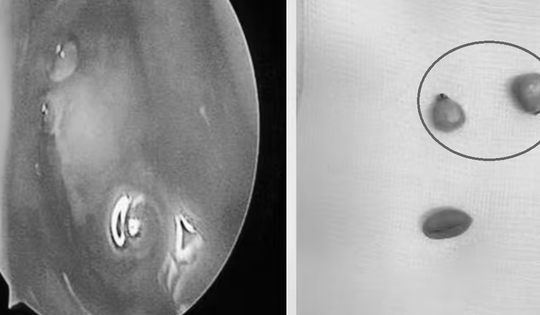

Gắp con vắt ký sinh một tuần trong mũi bé trai 2,5 tuổi

30/12/2025 19:46

Bé trai 2,5 tuổi theo cha mẹ lên rẫy tắm suối, về nhà suốt một tuần chảy máu mũi, khó thở, bác sĩ phát hiện con vắt ký sinh trong mũi.